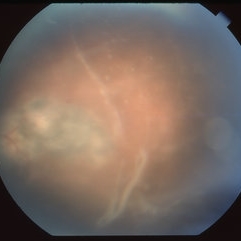

Thickening of the Posterior Hyaloid

Dec 12 2020 by Anyssa Montenegro

Color fundus photograph of the right eye of a 36-year-old man showing thickening of the posterior hyaloid associated with an epiretinal membrane due to ocular toxoplasmosis.

Photographer: Anyssa Montenegro, Centro Brasileiro da Visão, Brasília-DF, Brazil

Condition/keywords: epiretinal membrane (ERM), ocular toxoplasmosis, thickening of the posterior hyaloid